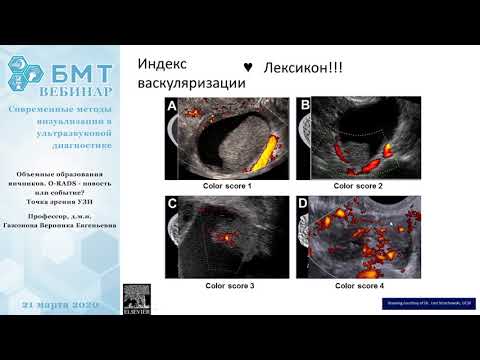

Объемные образования яичников. O-RADS с точки зрения УЗИ